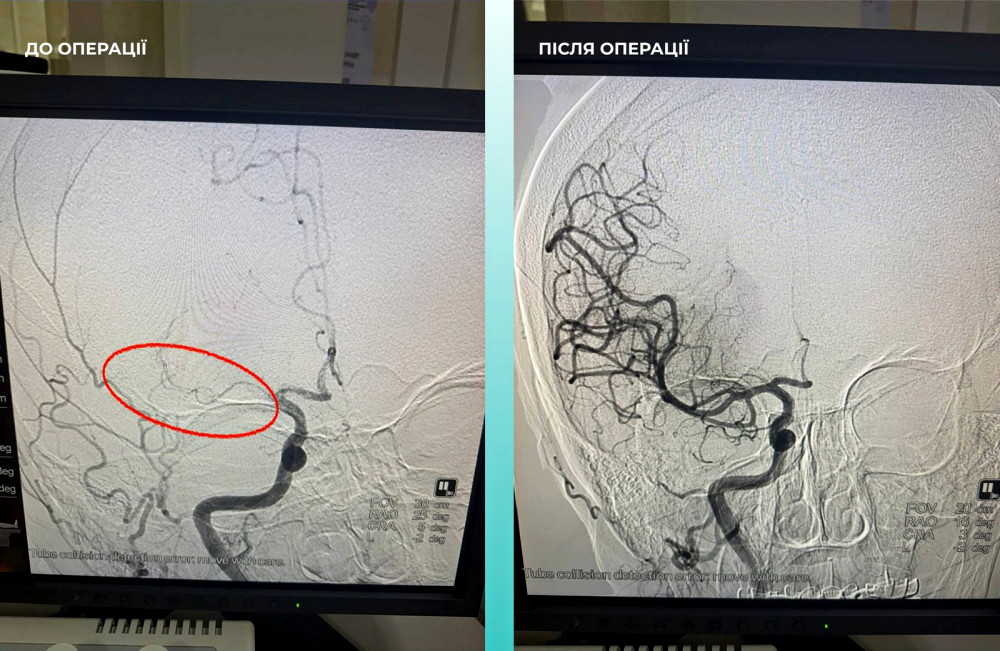

Пацієнтка потрапила в лікарню з серйозним гострим мозковим інсультом. Під час комп'ютерної томографії медики виявили закриття середньої мозкової артерії.

Команда фахівців ухвалила складне, але надзвичайно важливе рішення — провести одночасну тромбектомію для мозкових та легеневих артерій.

Операція пройшла успішно. Зараз пацієнтка почувається значно краще: вона при свідомості та вже може рухати кінцівками.